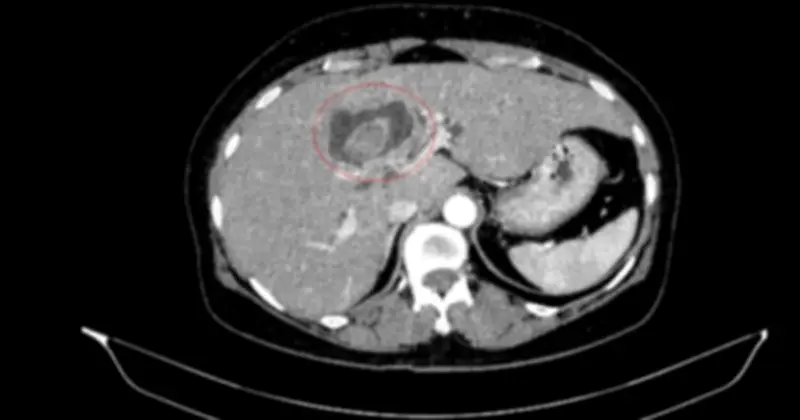

Một phụ nữ 59 tuổi đã được các bác sĩ tại Trung tâm Y học hạt nhân và Ung bướu, Bệnh viện Bạch Mai, tiếp nhận trong tình trạng vàng da, ngứa và đau vùng hạ sườn phải kéo dài. Kết quả chẩn đoán hình ảnh ban đầu cho thấy tổn thương đường mật trong gan kèm sỏi và giãn đường mật, nhưng quá trình thăm khám toàn diện đã phát hiện thêm một khối u tại đại tràng lên.

Sau khi tiến hành nội soi tiêu hóa, các bác sĩ đã phát hiện một khối u tại đại tràng lên. Kết quả sinh thiết xác định đây là ung thư biểu mô tuyến. Qua hội chẩn đa chuyên khoa, ê-kíp y tế xác định bệnh nhân mắc đồng thời hai ung thư nguyên phát, thay vì một khối u di căn như dự đoán ban đầu.

Cụ thể, ung thư đại tràng phải ở giai đoạn sớm, chưa di căn hạch, trong khi ung thư đường mật trong gan đã ở giai đoạn tiến triển, có xâm lấn và di căn hạch. Theo các chuyên gia, việc phân biệt ung thư nguyên phát với di căn có ý nghĩa then chốt, bởi nó quyết định hoàn toàn hướng điều trị và tiên lượng cho người bệnh.